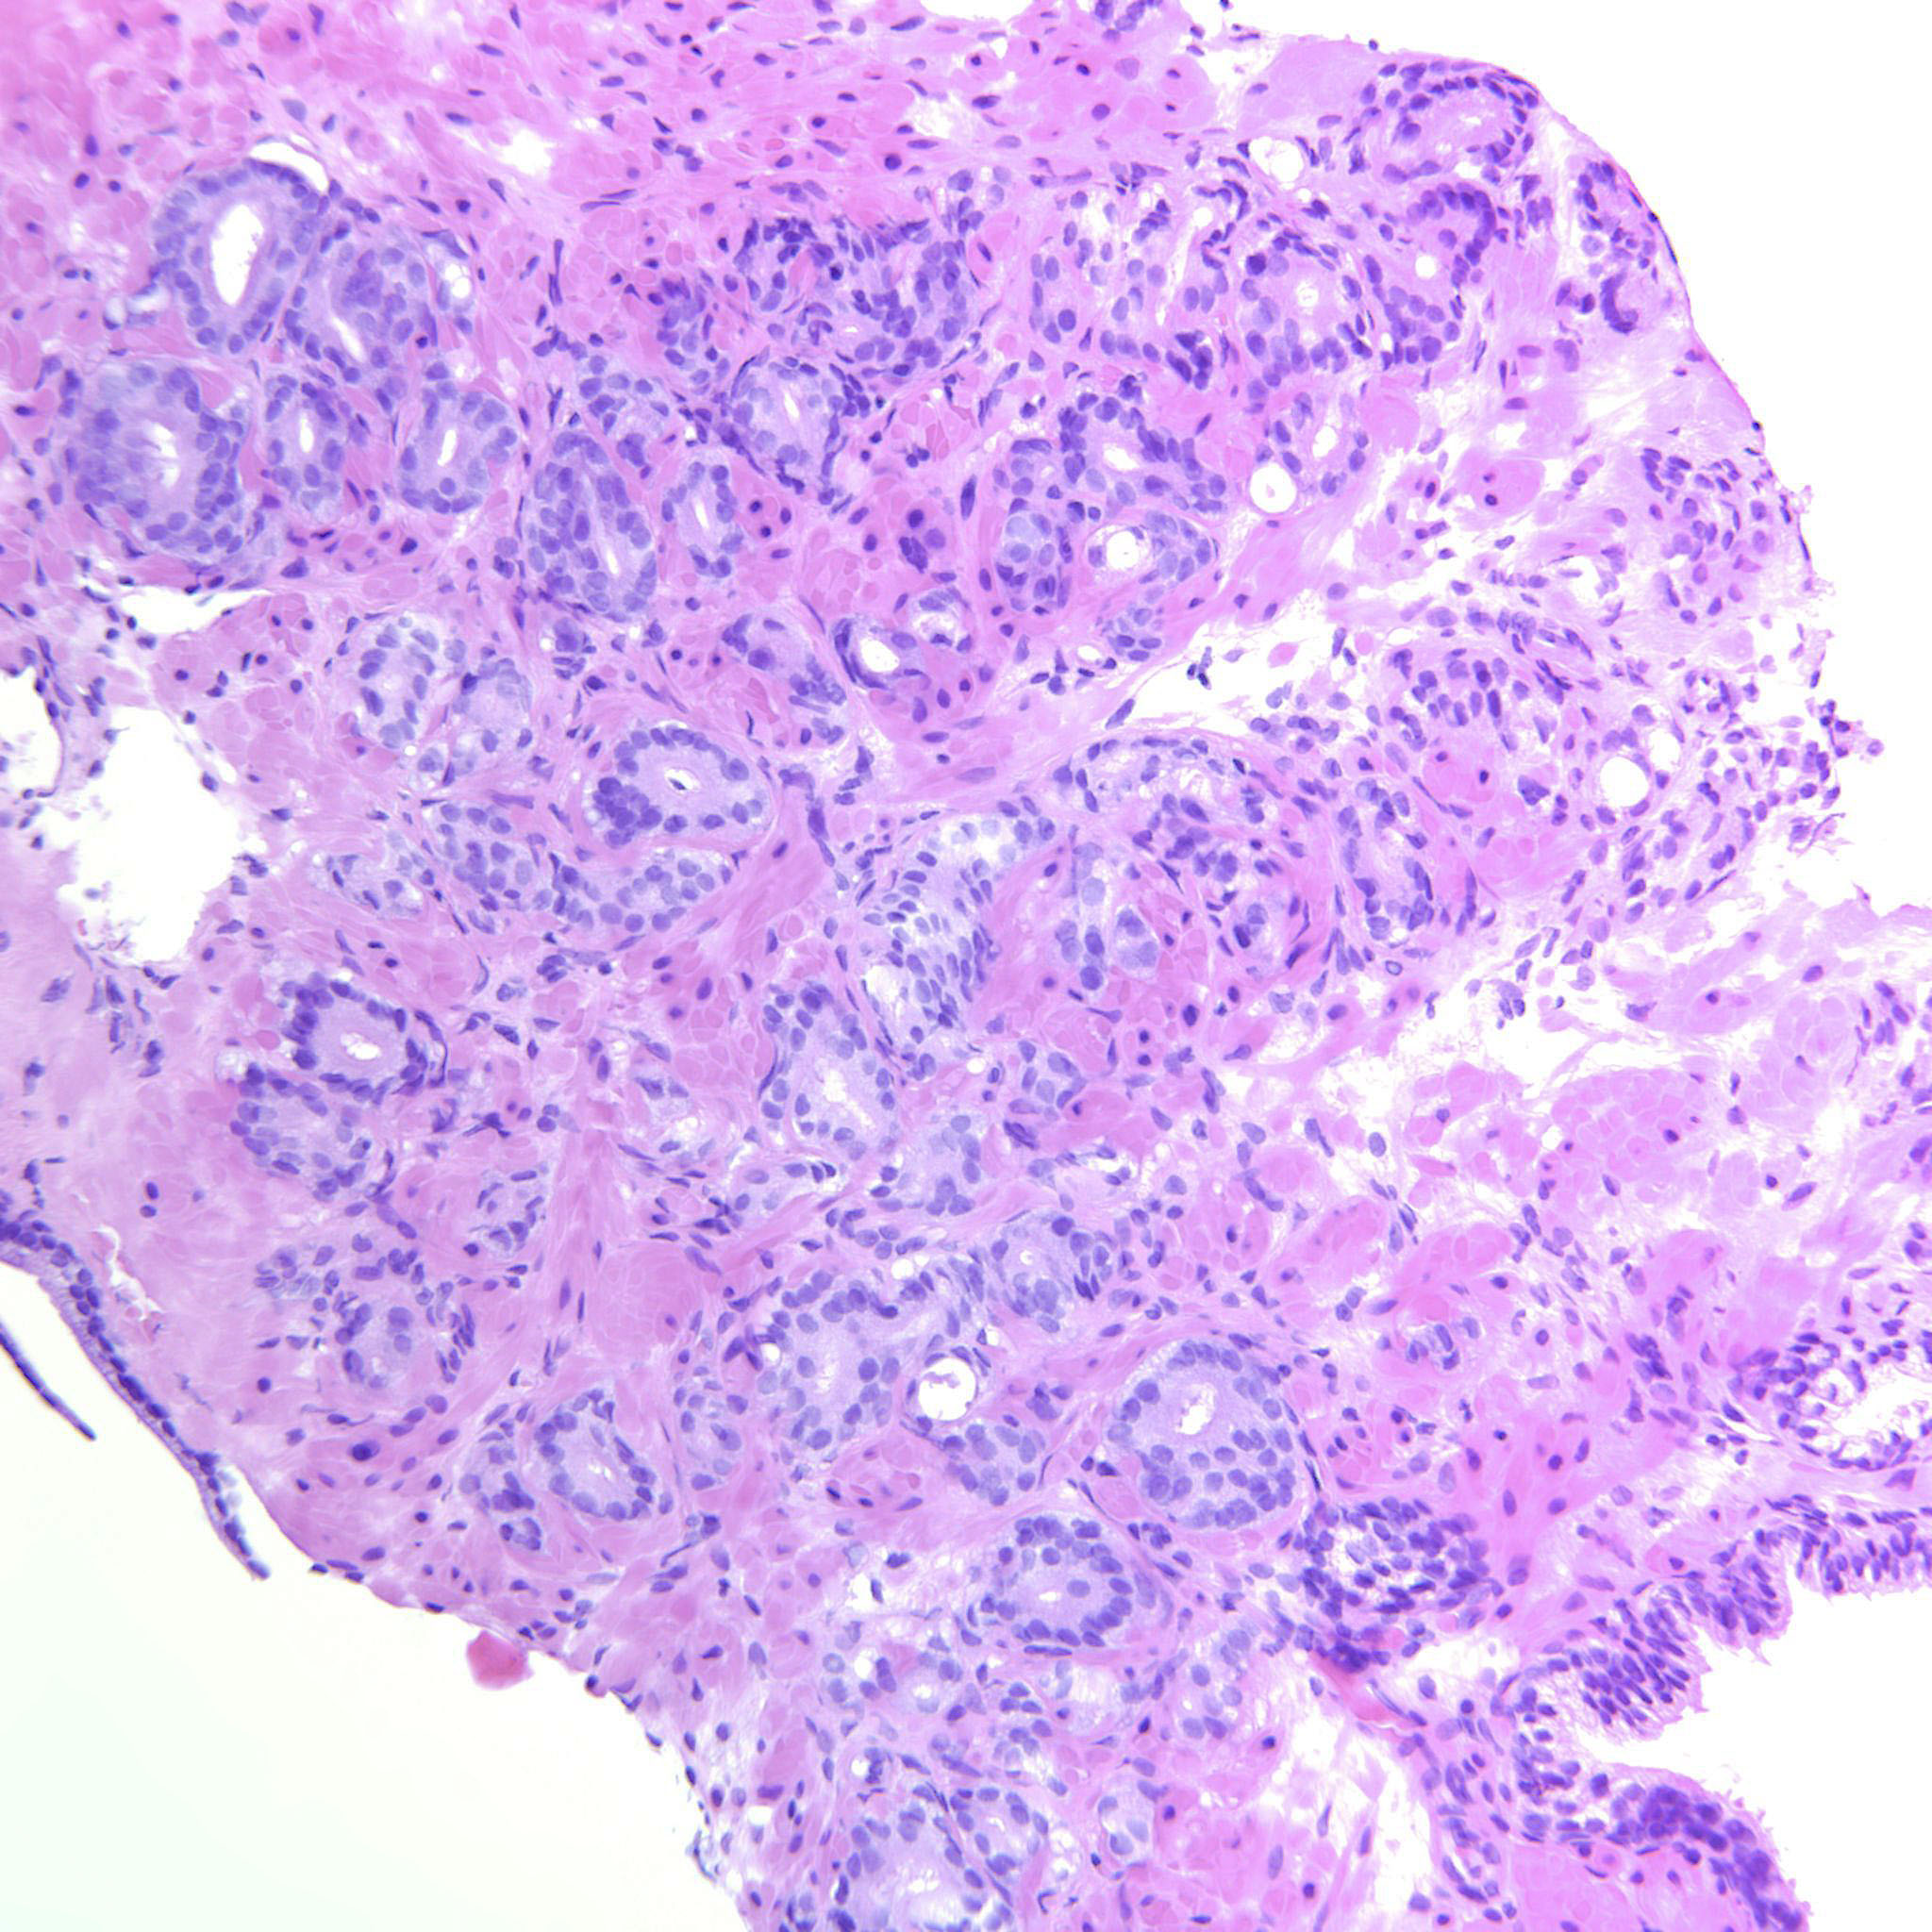

Prostate cancer grading

Case ID: 651